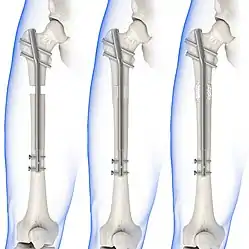

Treatment can be achieved by either non-operative (or conservative) or operative means. The main operative treatments for a Maisonneuve fracture are open-reduction surgery and closed-reduction surgery, both of which usually preceding internal fixation of the injury. These procedures are known as Open Reduction Internal Fixation (ORIF) and Closed Reduction Internal Fixation (CRIF).[6][13]

Internal fixators

Syndesmotic screws are the main, internal fixators used in surgeries for a Maisonneuve fracture. Two main types of syndesmotic screws are used: trans-syndesmotic screws (positioned at the level of the syndesmosis) and supra-syndesmotic screws (positioned above the syndesmosis).[14]

Based on several clinical results, syndesmotic screws are recommended to be fixed at least 1 centimetre proximal to the tibiofibular syndesmosis or 4 to 6 centimetres proximal to the tibiotalar joint line.[4][15] Cadaveric analyses, from a comparative study published in Foot & Ankle International in 1997, suggest that screw fixation at 2 centimetres proximal to the tibiotalar joint line is also adequate.[16] Biodegradable implants such as bioabsorbable screws, which do not require postoperative removal, may be used as an alternative to metallic hardware. However, biodegradable implants still limit rotation of the ankle and dorsiflexion of the foot.[4][6][13]